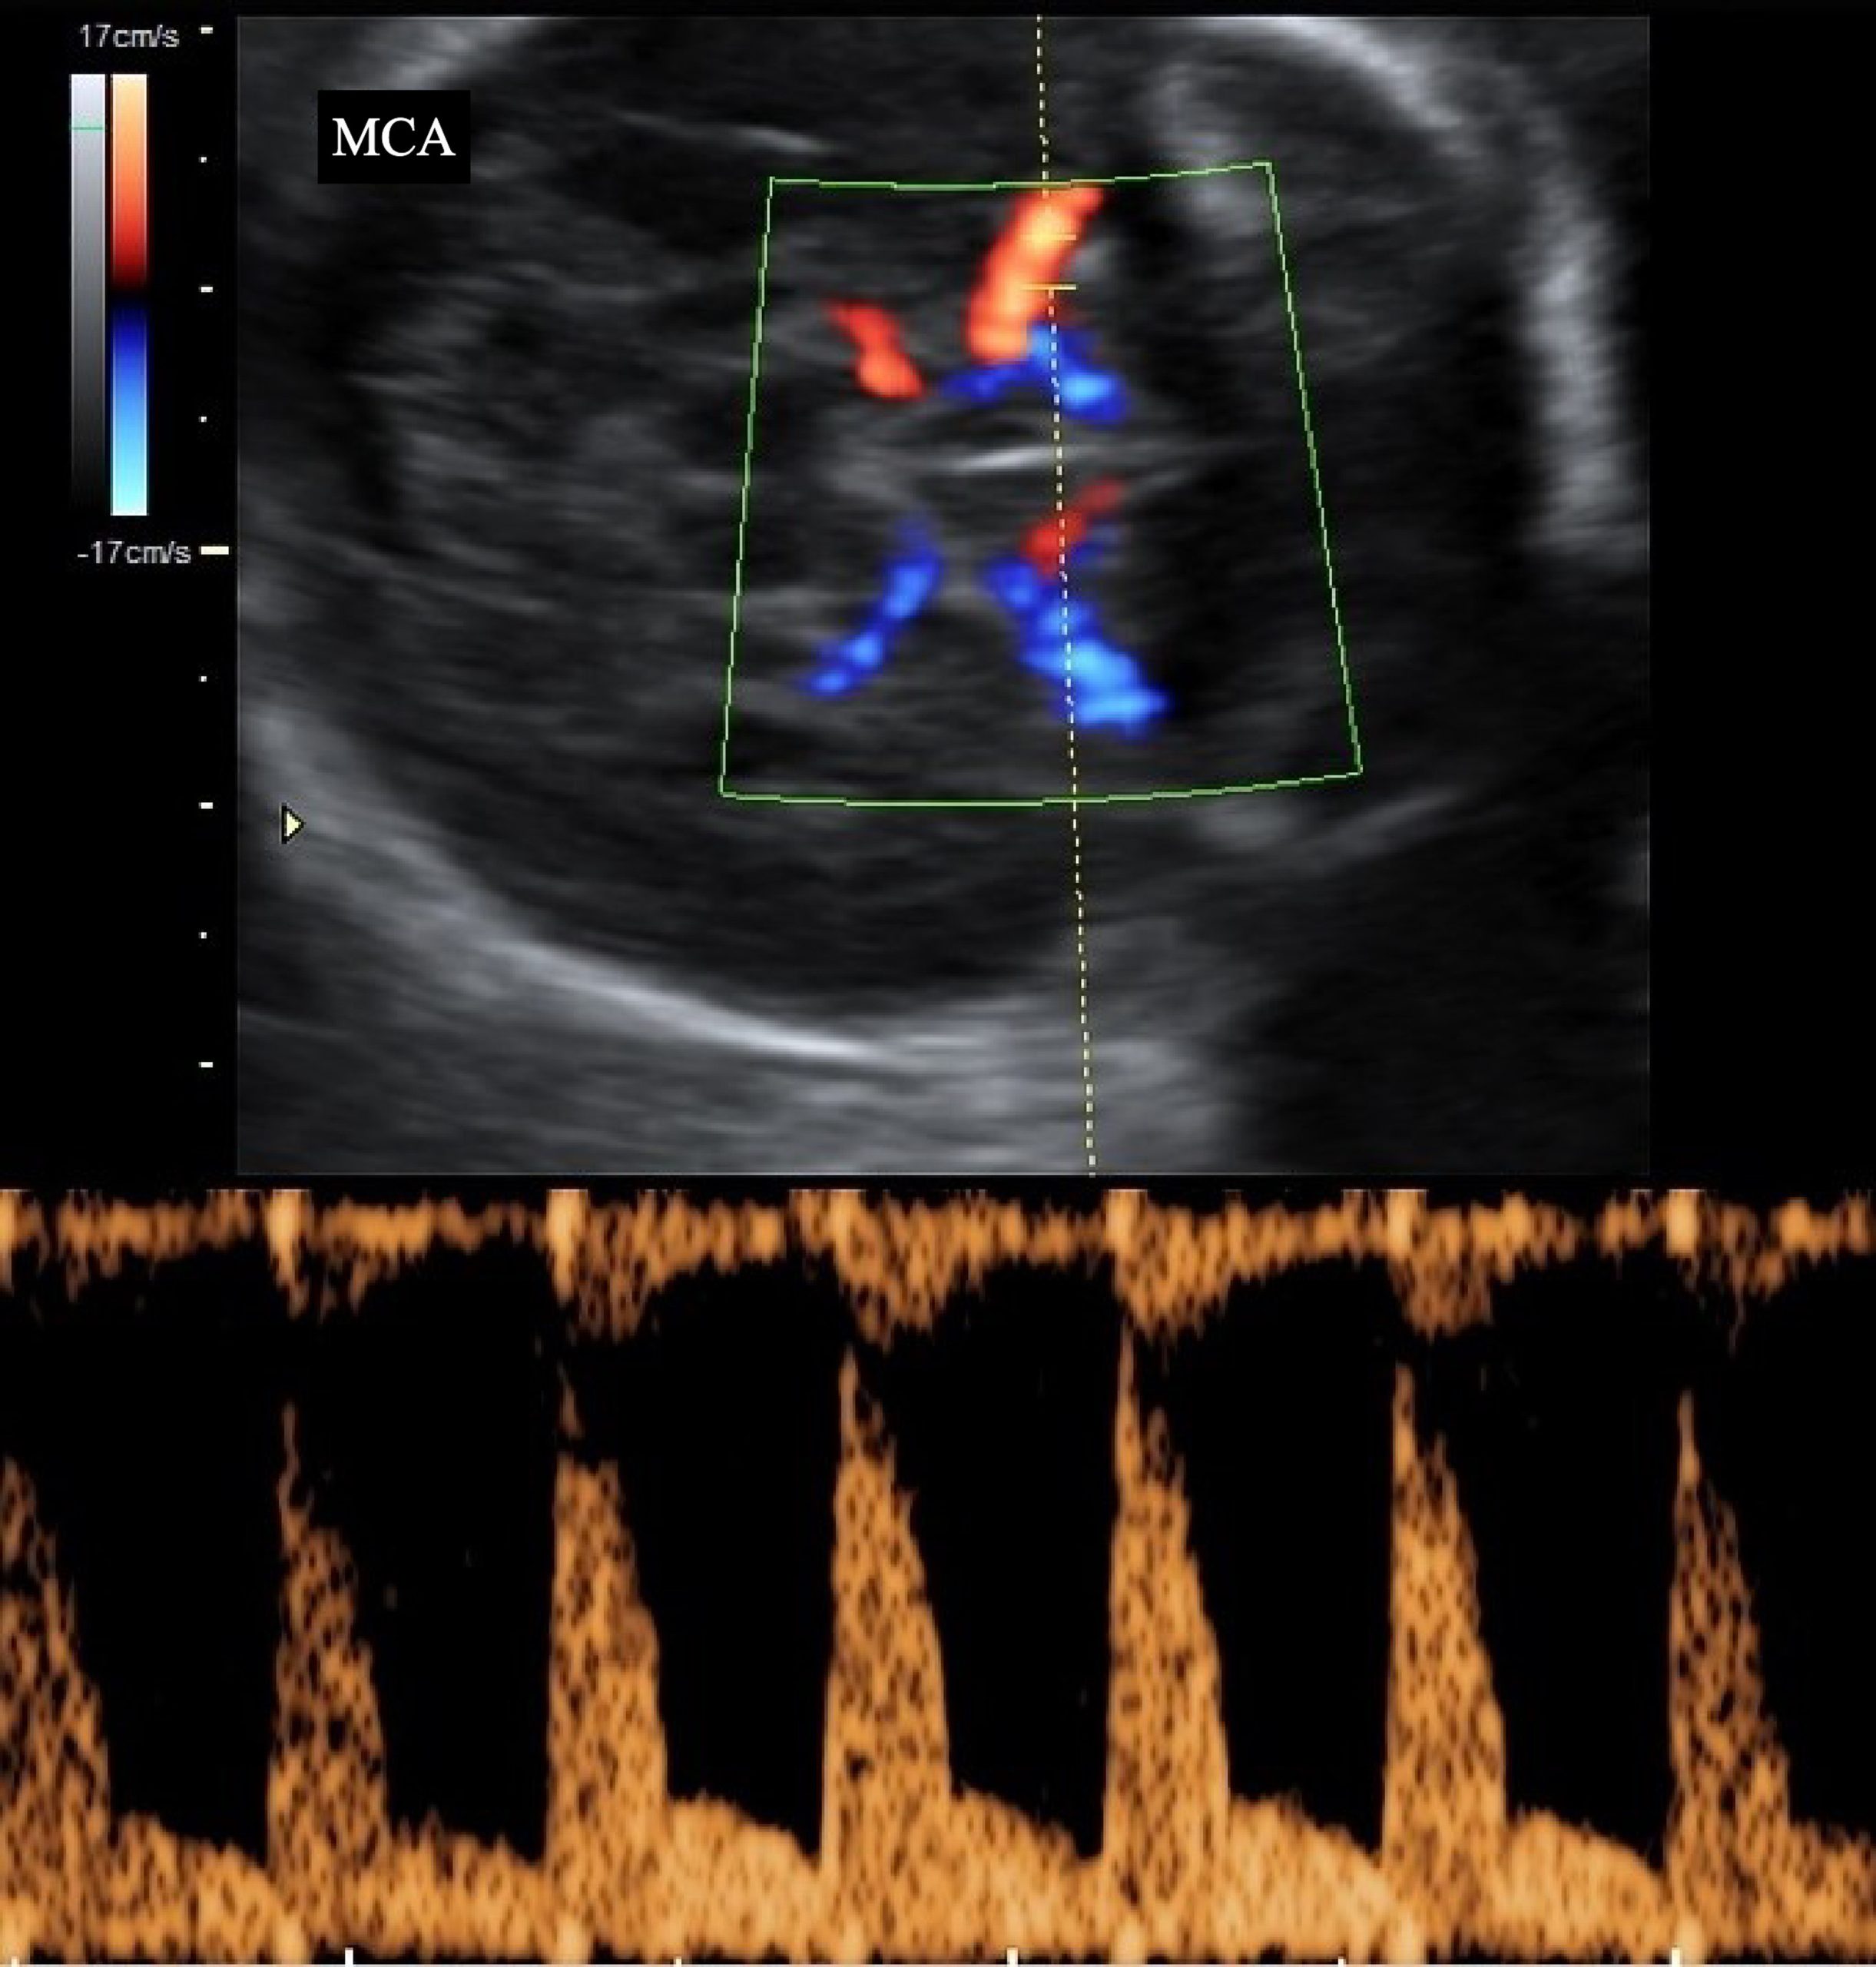

Doppler Obstétrico

Se realiza dentro de las 28 a 36 semanas de gestación. Combinamos lo mejor de la tecnología para detectar enfermedades. Agenda una cita para una Ecografía Doppler para un análisis de la circulación materna y fetal.

Este es un método rápido y no invasivo cuya evaluación permite asegurar el bienestar fetal porque mide los parámetros hemodinámicos fetales.

Además de los siguientes puntos, en EcoQ Ultrasonidos Quiñones, también nos enfocamos en la fetometría, posición de la placenta, cordón y líquido amniótico.

Ultrasonido Estructural Gemelar 3er Trimestre (Curva de Crecimiento y/o Doppler Obstétrico)

Descarta el 70% de los defectos cardíacos congénitos con un ultrasonido de embarazo gemelar y evalúa la correcta oxigenación de tus bebés.

En EcoQ Ultrasonidos Quiñones analizamos el estado de tus gemelos, como la placenta y la bolsa amniótica para evitar condiciones como las siguientes:

- Arteria cerebral media

- Arteria umbilical

- Ductus venoso

- Regurgitación tricuspídea

- Índice cerebro-placentario

- Índice de pulsatilidad de arterias uterinas

- Posición de ambos gemelos